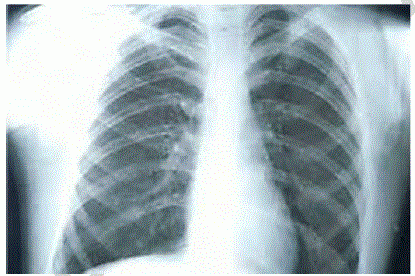

Um paciente etilista deu entrada no pronto-socorro com intensa dor em região torácica, associada a vômitos, após realizar grande esforço. A dor é localizada em região retroesternal e em abdome superior, de início agudo e de forte intensidade. Quanto a comorbidades, informa tratamento para úlcera gástrica há um ano. Queixa-se de odinofagia associado ao quadro de dor no peito. Ao exame fisico, constatam-se abdome doloroso sem sinal de irritação peritoneal, PA = 150 mmHg x 100 mmHg, FC = 130 bpm, FR = 30 irpm e SatO2 = 93% AA. Realizou raios X de tórax, representado na imagem a seguir.

Esse paciente apresenta a chamada síndrome de Boerhaave.